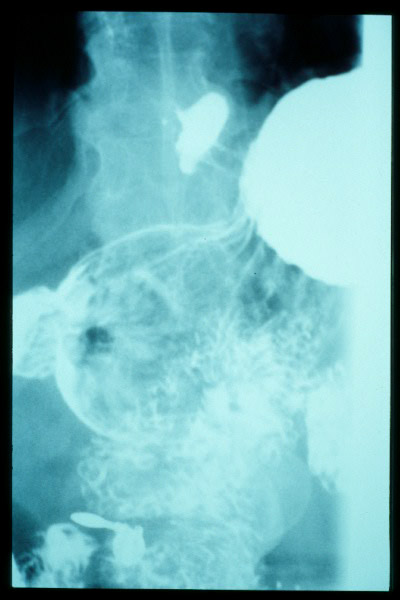

Hernia de hiato gigante.